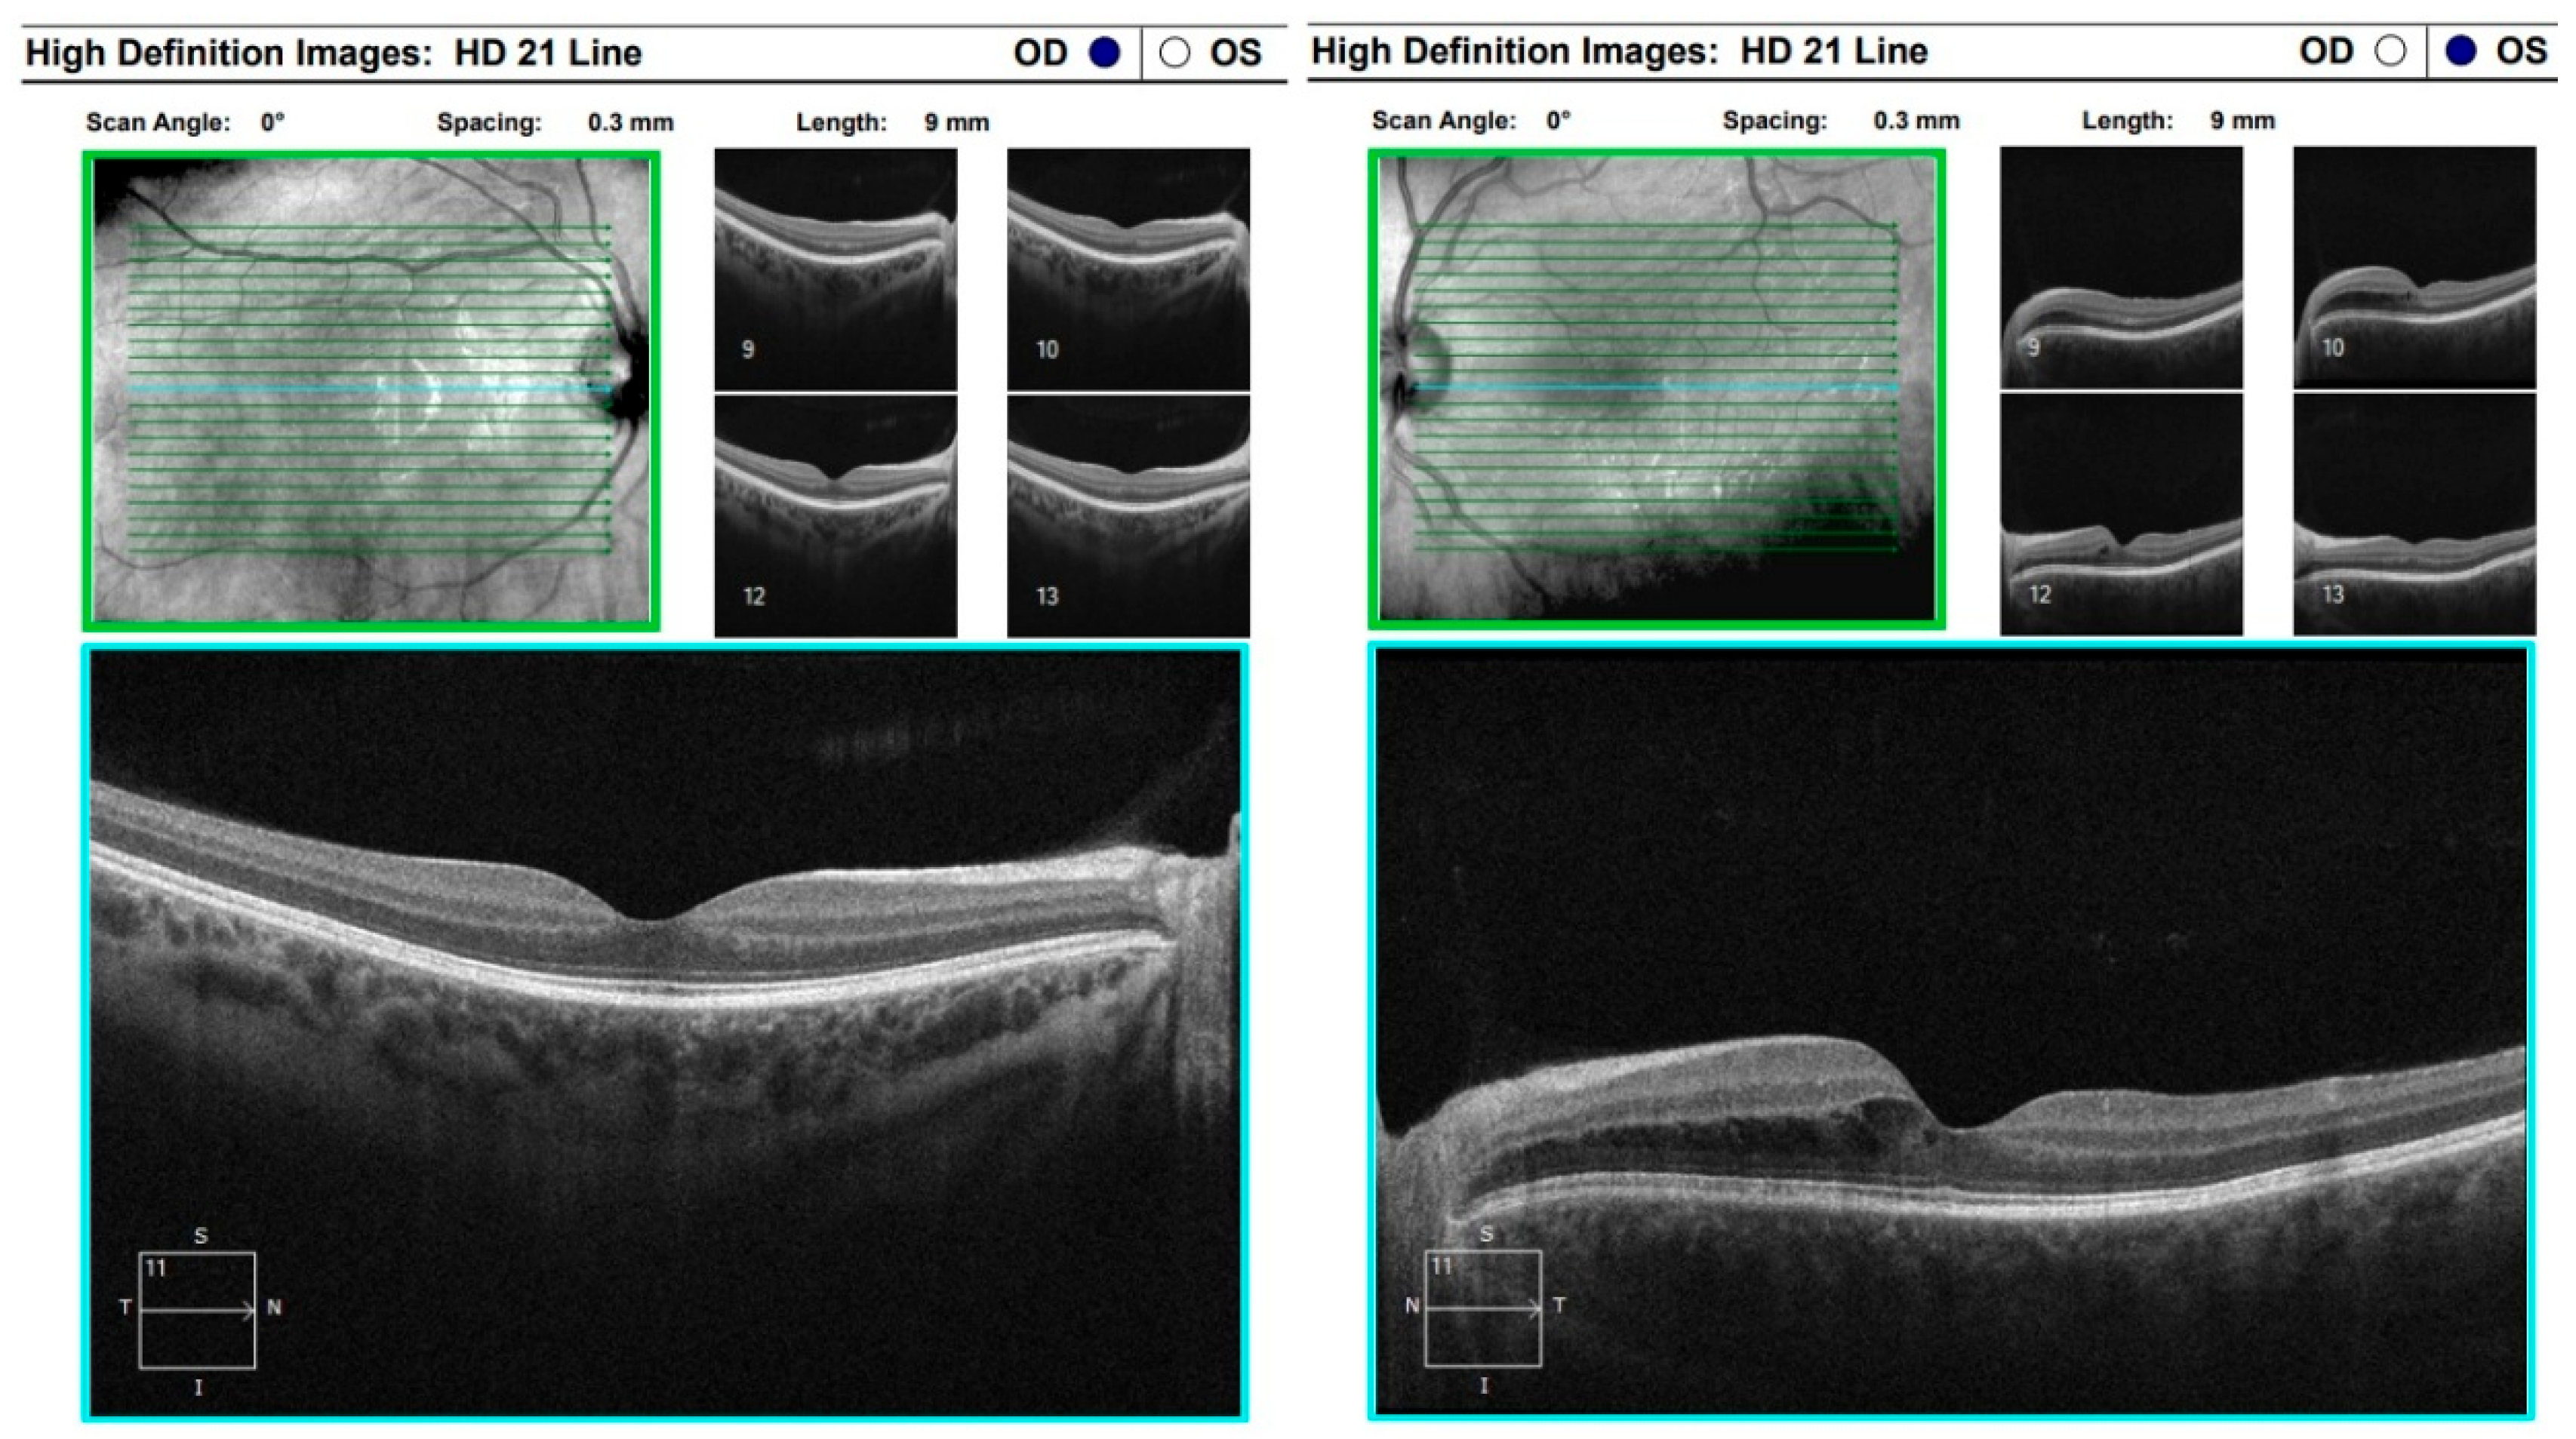

Three days later, the patient reported a sharp decline in visual acuity, which necessitated a follow-up visit. The visual acuity of the right eye had dropped to 0.04, and in the left eye—she could count fingers in front of the eye. The conjunctiva was bilaterally chemotic, and fine precipitates were observed on the corneal endothelium (Arlt’s triangle). The intraocular pressure was normalized: TOD = 10.8 mmHg, TOS = 12.1 mmHg. From ophthalmoscopy—both maculae had a yellowish reflex, and the exudative retinal detachment in the mid-periphery persisted. From the performed FAG, bilaterally dilated vessels with increased tortuosity, punctate hyperfluorescence in the macula and in the mid-periphery, increasing in intensity and area in the late phases—a sign of edema. (Figure 8) In addition, areas of patchy hypo- and hyperfluorescence are visualized in the mid-periphery bilaterally—areas of exudative retinal detachment. (Figure 9) The patient was referred for emergency hospitalization to initiate intravenous corticosteroid therapy in order to influence the chorioretinal inflammation bilaterally.

Figure 9. FA (fluorescein angiography).